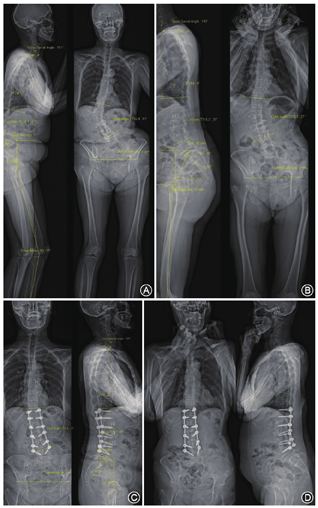

典型病例具体资料请见图1。

一期手术前后及末次随访时的放射学测量结果见表1。一期手术后和末次随访时,患者Cobb角、矢状面平衡参数均明显改善(均P<0.01)。提示腰椎微创侧路椎体间融合术(LLIF/OLIF)可明显改善成人退变性脊柱侧弯患者的冠状面畸形和矢状面平衡。

患者男6例,女17例,平均年龄(72±4)岁(62~79岁)。9例患者采用LLIF手术,14例采用OLIF手术。16例植入3个融合器,5例植入2个融合器,2例植入4个融合器。平均随访24.2个月(15~42个月)。一期手术后,患者侧弯Cobb角(18°±7°)较术前(33°±8°)明显改善(t=13.2,P<0.01);PI-LL(20°±8o比31°±8o)、SVA[(5.3±2.0)cm比(8.2±3.5)cm)、PT(16°±6°比23°±4°)等矢状面参数均较术前明显改善(t=6.8、4.5、9.0,均P<0.01)。患者末次随访时腰痛VAS评分(3.4±1.1比6.3±1.0)和ODI指数(27.3%±3.0%比47.1%±5.9%)也均显著改善(t=11.3、17.8,均P<0.01)。全组无严重并发症发生。

23例患者中,男6例,女17例,平均年龄(72±4)岁(62~79岁)。平均随访时间24.2个月(15~42个月)。其中有9例患者采用LLIF手术,14例患者采用OLIF手术。23例患者中,16例植入3个融合器,5例植入2个融合器,2例植入4个融合器。手术节段:L4/5 18个,L3/4 23个,L2/3 21个,L1/2 4个。5例因一期手术矢状面平衡矫正不满意在二期行L4/5和(或)L5/S1的经关节突截骨,无患者需在二期进行经椎弓根椎体截骨(PSO)或更高级别的截骨矫形术。一期手术后,无患者因为神经根压迫症状而需要进行后路手术直接减压。